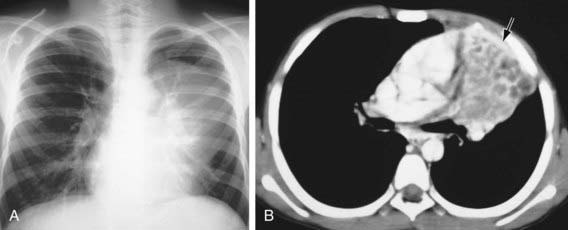

Pulmonary tumors may manifest as fever, hemoptysis, wheezing, cough, pleural effusion, chest pain, dyspnea, or recurrent or persistent pneumonia or atelectasis. Tumors may be suspected from plain chest radiographs; CT scanning of the chest is necessary for precise anatomic definition (Fig. 403-1). Bronchial tumors are occasionally diagnosed during fiberoptic bronchoscopy performed for persistent or recurrent pulmonary infiltrates or for hemoptysis.

Figure 403-1 Endobronchial mucoepidermoid carcinoma in a 10 yr old boy who presented with cough and fever. A, The chest radiograph shows a left upper lobe mass, a hyperinflated left lower lobe, and a prominent left hilum. B, The CT scan shows complete obstruction of the left upper lobe bronchus by a low-attenuation mass that extends into the left mainstem bronchus.

(From Slovis TL, editor: Caffey’s pediatric diagnostic imaging, ed 11, vol 1, Philadelphia, 2008, Mosby.)